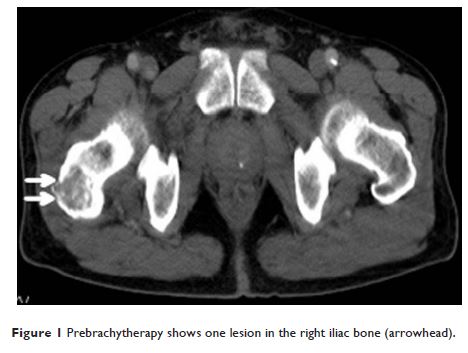

125I 种子源与外照射放疗对一周期化疗后肺癌骨转移疼痛缓解的作用对比